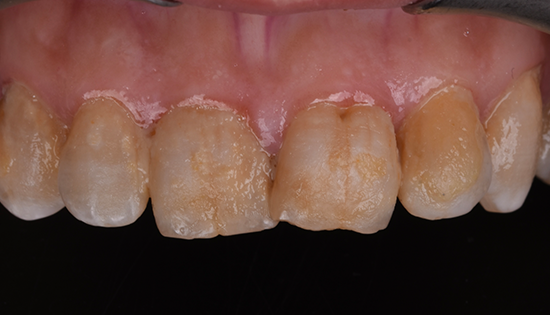

يلجأ الشخص إلى تحسين شكل أسنانه عن طريق فينير الأسنان أو ما يطلق عليه (عدسات الأسنان اللاصقة) وهي عبارة قشرة رقيقه يتم لصقها على السطح الخارجي للأسنان مصنوعة من مواد صلبة ذات معامل شفافيه مطابق للأسنان الطبيعيه   لعلاج مشكلة الاصفرار أو عدم التساوي والعديد من المشاكل الأخرى، حتى يحصل الشخص على ابتسامة رائعة تشبه ابتسامة نجوم هوليود.

•  تغير لون الأسنان الطبيعية من اللون الأبيض للون الأصفر.

• تكسر وتشقق الأسنان.

• عدم تناسق الأسنان او اعوجاجها.

• وجود حشوات عديده بالأسنان الأماميه ذات مظهر سيء.